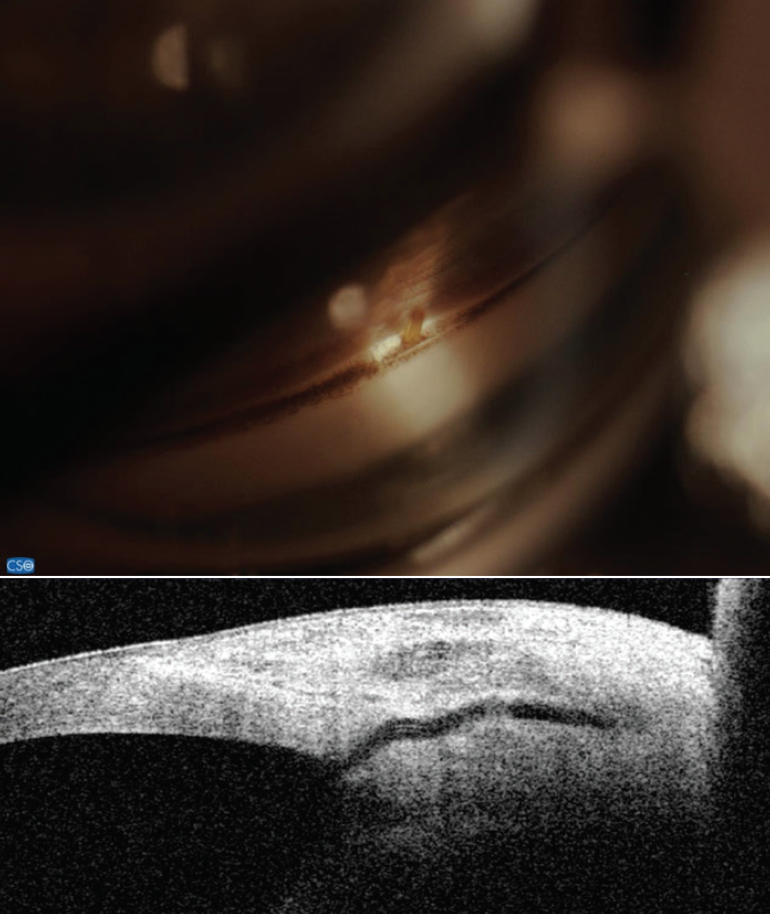

Figure 7. The Xen Gel Stent with corresponding views in the angle and on anterior segment OCT. Note the short length in the anterior chamber and the distance from the cornea. Dimensions: overall length = 6 mm, outer diameter = 150 μm (expands to 220 μm when hydrated), and inner diameter = 45 μm.

So far, there are few data with regard to subconjunctival MIGS devices. For the Xen Gel Stent (Allergan), a small nonrandomized, retrospective study of 11 patients showed no change in ECD at 12 months.15 No data are available for the InnFocus MicroShunt (Santen).